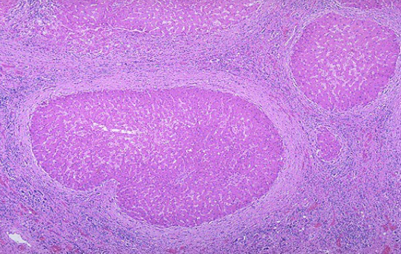

病理变化:肉眼观,肝体积显著缩小,尤以左叶为甚,重量减至600~800g,质地柔软,表面被膜皱缩。切面呈黄*色或红褐色,有的区域呈红黄相间的斑纹状,故又称急性黄*色肝萎缩或急性红色肝萎缩。镜下见肝细胞呈一次性大块坏死(坏死面积≥肝实质的2/3)或亚大块坏死。肝索解离,肝细胞溶解,仅小叶周边部残留少数变性的肝细胞。肝窦明显扩张充血并出血,库普弗细胞增生肥大,并吞噬细胞碎屑及色素。小叶内及门管区有淋巴细胞和巨噬细胞为主的炎细胞浸润。残留的肝细胞再生现象不明显。

(2)亚急性重型肝炎:多数是由急性重型肝炎迁延而来或一开始病变就比较缓和呈亚急性经过。少数病例可能由普通型肝炎恶化而来。本型病程可达一至数月。病变特点是既有大片的肝细胞坏死,又有肝细胞结节状再生。由于坏死区网状纤维支架塌陷和胶原纤维化,致使再生的肝细胞失去原有的依托呈不规则的结节状,失去原有小叶的结构和功能。小叶内外有明显的炎细胞浸润。小叶周边部小胆管增生并可有胆汁淤积形成胆栓。肉眼观,肝不同程度缩小,被膜皱隔,呈黄绿色(亚急性黄*色肝萎缩)。病程长者可形成大小不等的结节,质地略硬。切面黄绿色(胆汁淤积),交错可见坏死区及小岛屿状再生结节。此型肝炎如及时治疗有停止进展和治愈的可能。病程迁延较长(如1年)者,则逐渐过渡为坏死后性肝硬化。病情进展者可发生肝功能不全。